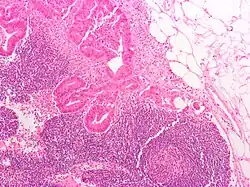

O tipo do tumor é geralmente diagnosticado através da análise de tecido removido através de uma biópsia ou cirurgia. O diagnóstico patológico geralmente contém a descrição histológica do cancro, e o grau. O tipo mais comum de cancro colorretal é adenocarcinoma, que compõe 95% dos casos - acredita-se que a maioria dos casos de cancro colorretal envolvam tumores originários de pólipos adematosos. Outros tipos, mais raros, de cancro colorretal, incluem linfoma e carcinoma espinocelular. As causas do cancro colorretal não são conhecidas com exatidão no presente.

Adenocarcinoma é um tipo de tumor maligno epitelial, que se origina do epitélio glandular da mucosa colorretal. Tal tumor invade a parede, infiltrando a mucosa muscular, a submucosa, e daí, a muscularis propria. As células do tumor abrigam estruturas tubulares irregulares, de estrutura pluristratificada, lúmens múltiplos, e estromas reduzidos. Por vezes, as células do tumor secretam muco, que invade o fluido intersticial, produzindo grandes agrupamentos de muco e colóide (que, visualmente, aparecem como "espaços vazios") - é o chamado adenocarcinoma colóide, pouco diferenciado. Se o muco permanece dentro da célula do tumor, o muco empurra o núcleo celular para a periferia da célula - célula do tipo signet-ring. Dependendo da arquitetura glaudular, pleomorfismo celular, e padrão da secreção de muco, o adenocarcinoma pode ser categorizado em três graus de diferenciação: bem diferenciado, moderadamente diferenciado, e mal diferenciado.[48]